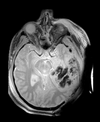

Slicer Registration Library Case 38: TBI

| T1pre | FLAIR | T1post | coronal T2 | SWI | EP50 | EP75 | EP100 |